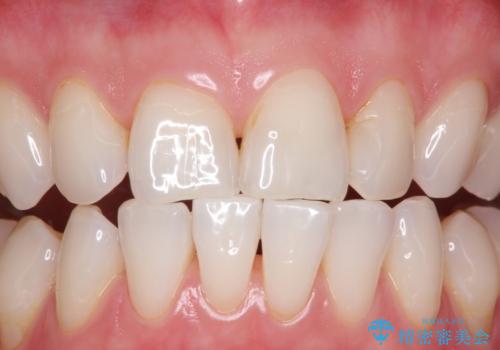

インビザライン中の方へブラッシング指導

- インビザラインにて矯正治療中の方です。矯正治療の経過チェック時に歯磨き指導とクリーニングも希望とのことでした。

PMTC30分コースを行いました。